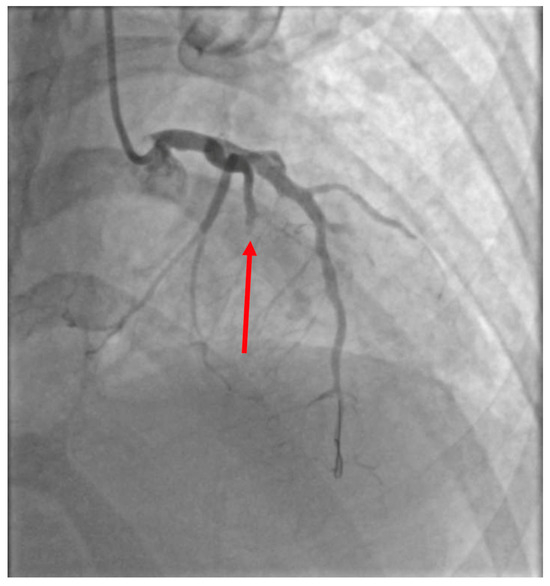

Cardiac catheterization confirmed a 100% left circumflex artery occlusion, and a stent was placed to restore perfusion (Figure 1). For anticoagulation, she was started on a continuous heparin infusion and aspirin 81 mg following stent placement, then transitioned to apixaban 5 mg twice daily and continued on aspirin at discharge. In-patient, she was given IV methylprednisolone 125 mg daily for 6 days.

• Cardiac catheterization confirmed a 100% left circumflex artery occlusion (Figure 1).

At the end of a 4 h 1 g rituximab infusion, the patient developed sudden, severe substernal chest pain. Vitals were stable, but the ECG showed new ST elevations. Troponin was significantly elevated, peaking at 72,000 ng/L. Emergent cardiac catheterization revealed 100% occlusion of the left circumflex artery; a drug-eluting stent was placed (Figure 1). No evidence of underlying atherosclerosis was noted.

Figure 1. Coronary angiogram showing 100% left circumflex artery occlusion (red arrow).